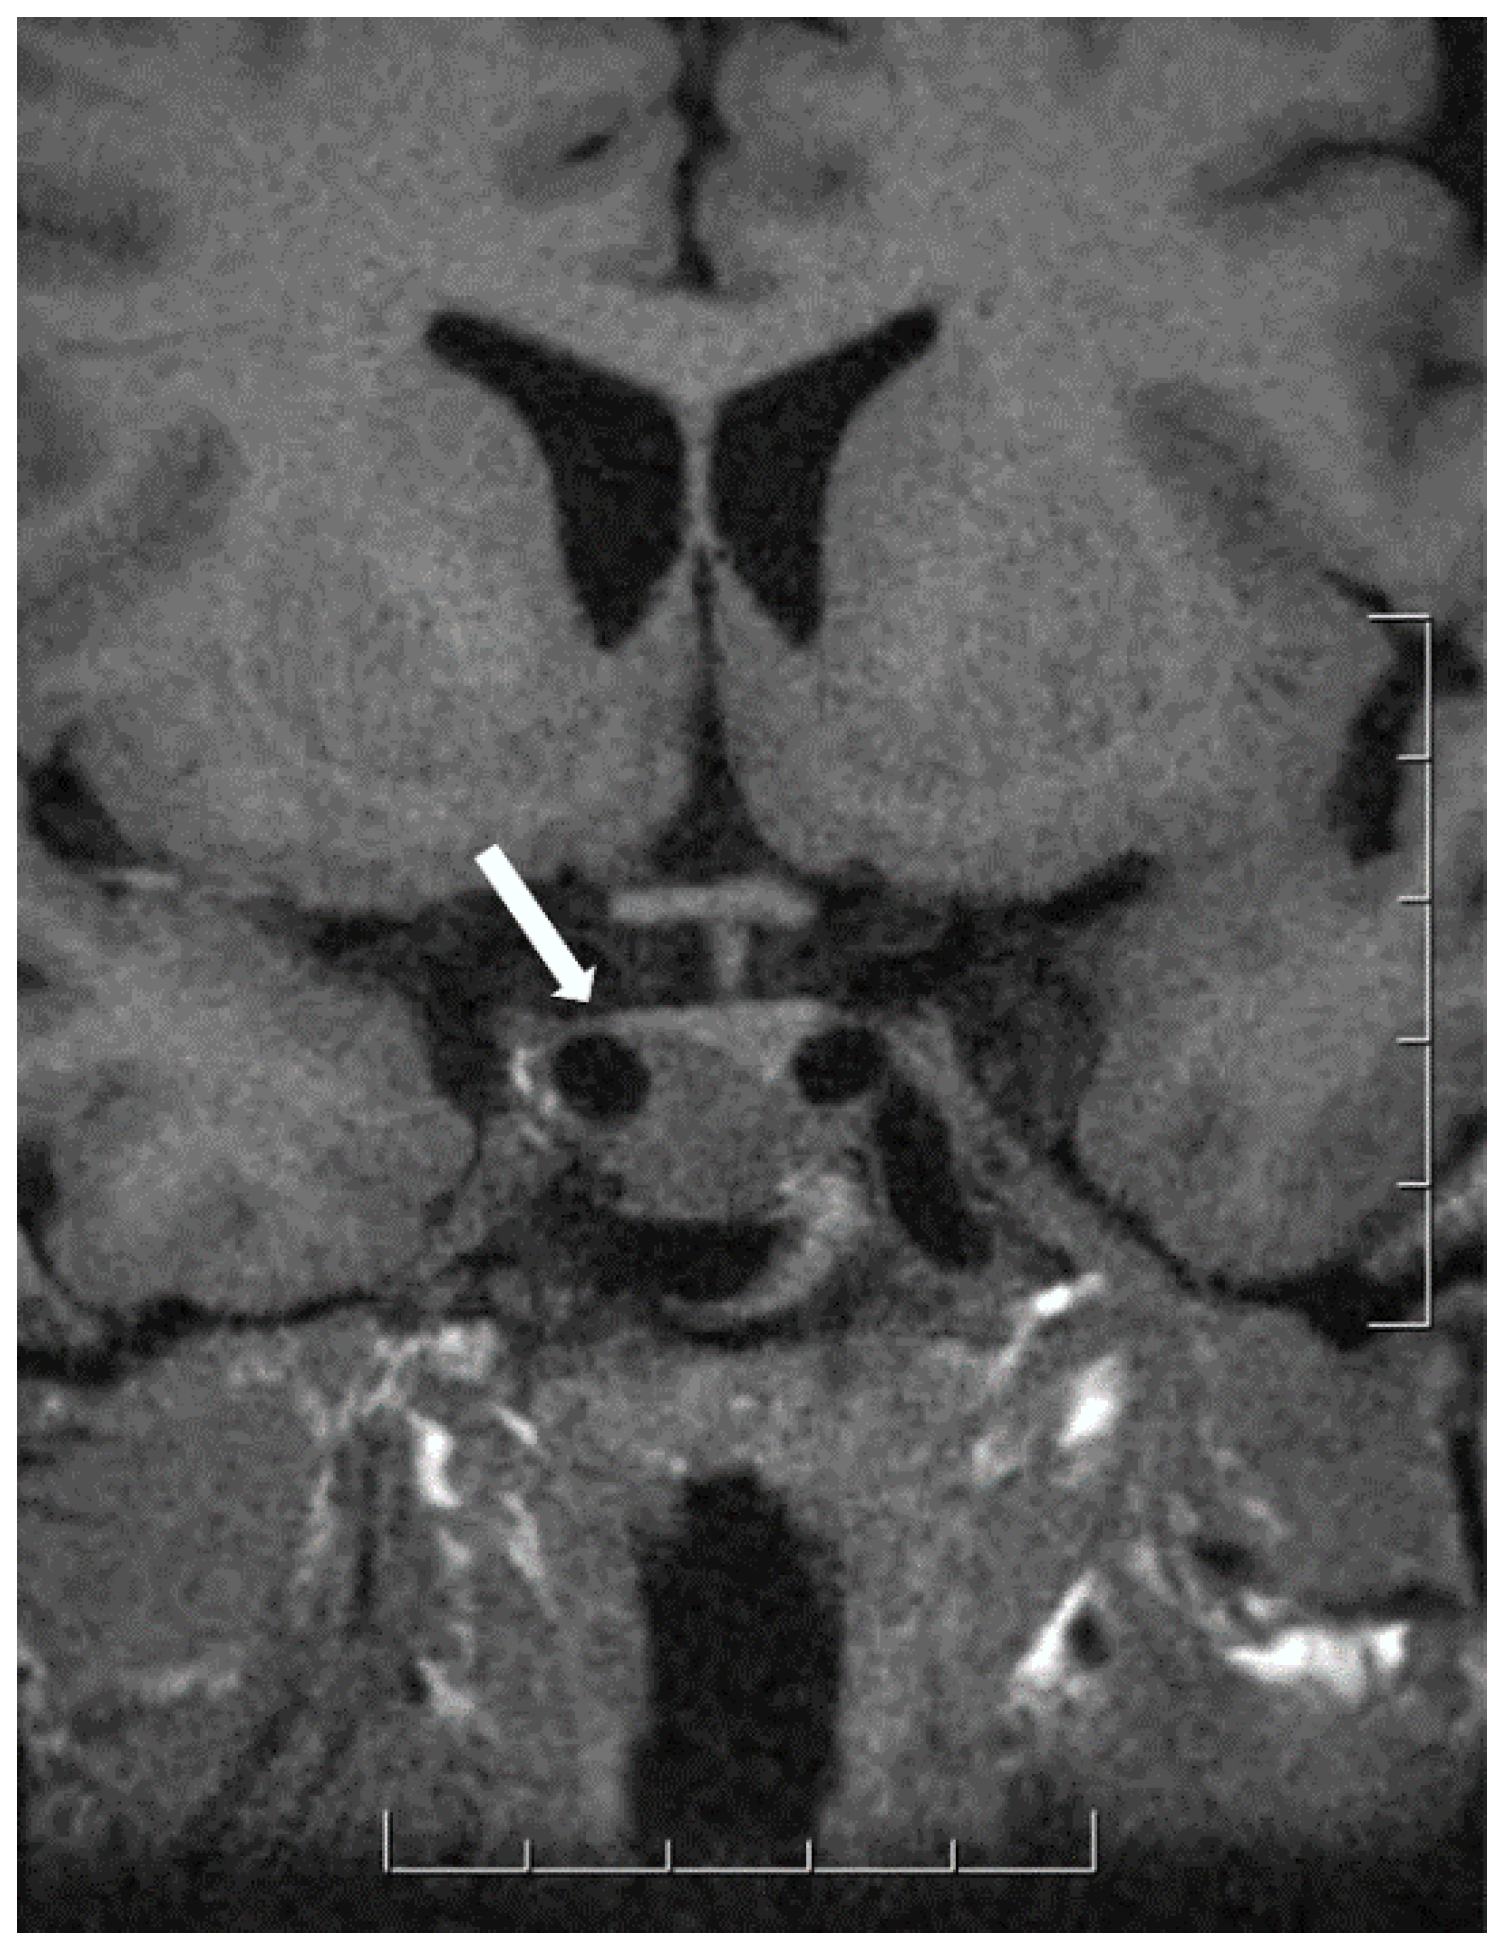

5. Hypothalamic Tumors

- Asa, S.L.; Mete, O. Hypothalamic Endocrine Tumors: An Update. J. Clin. Med. 2019, 8, 1741. [Google Scholar] [CrossRef]

- Hassoun, J.; Gambarelli, D.; Grisoli, F.; Pellet, W.; Salamon, G.; Pellissier, J.F.; Toga, M. Central neurocytoma. An electron-microscopic study of two cases. Acta Neuropathol. 1982, 56, 151–156. [Google Scholar] [CrossRef] [PubMed]

- Louis, D.N.; Ohgaki, H.; Wiestler, O.D.; Cavanee, W.K. World Health Organization Histological Classification of Tumours of the Central Nervous System; International Agency for Research on Cancer: Lyon, France, 2016. [Google Scholar]

- Asa, S.L.; Ezzat, S.; Kelly, D.F.; Cohan, P.; Takasumi, Y.; Barkhoudarian, G.; Heaney, A.P.; Ridout, R.; Chik, C.L.; Thompson, L.D.R.; et al. Hypothalamic vasopressin-producing tumors: Often inappropriate diuresis but occasionally cushing disease. Am. J. Surg. Pathol. 2018, 42, 251–260. [Google Scholar] [CrossRef]

- Araki, Y.; Sakai, N.; Andoh, T.; Yoshimura, S.; Yamada, H. Central neurocytoma presenting with gigantism: Case report. Surg. Neurol. 1992, 38, 141–145. [Google Scholar] [CrossRef]